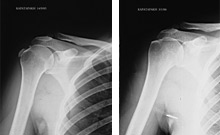

Παραθέτουμε τις ακτινογραφίες.

Η εναπόθεση ασβεστίου φαίνεται καθαρά στις ακτινογραφίες αριστερά, ενώ αυτές δεξιά έχουν ληφθεί μετά την εφαρμογή της θεραπείας όπου το ασβέστωμα έχει εξαλειφθεί.